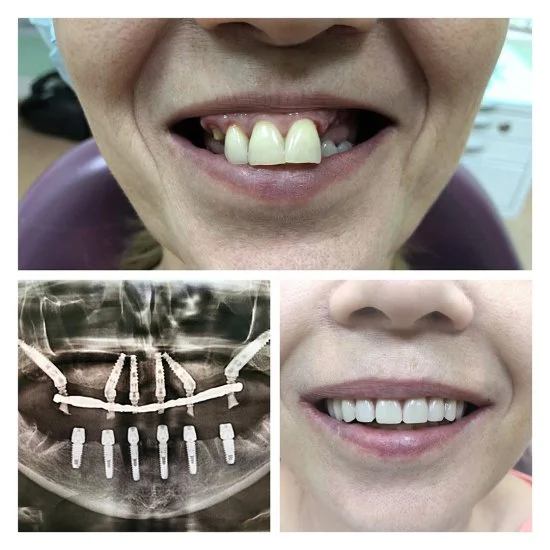

Andrey to doświadczony chirurg stomatolog z ponad 24-letnim stażem. Zajmuje się usuwaniem zębów i implantacją także w trudnych przypadkach — nawet wtedy, gdy inni lekarze nie podejmują się leczenia. Dzięki wiedzy i praktyce potrafi przeprowadzić skomplikowane zabiegi tak, żeby efekt był pewny i przewidywalny.